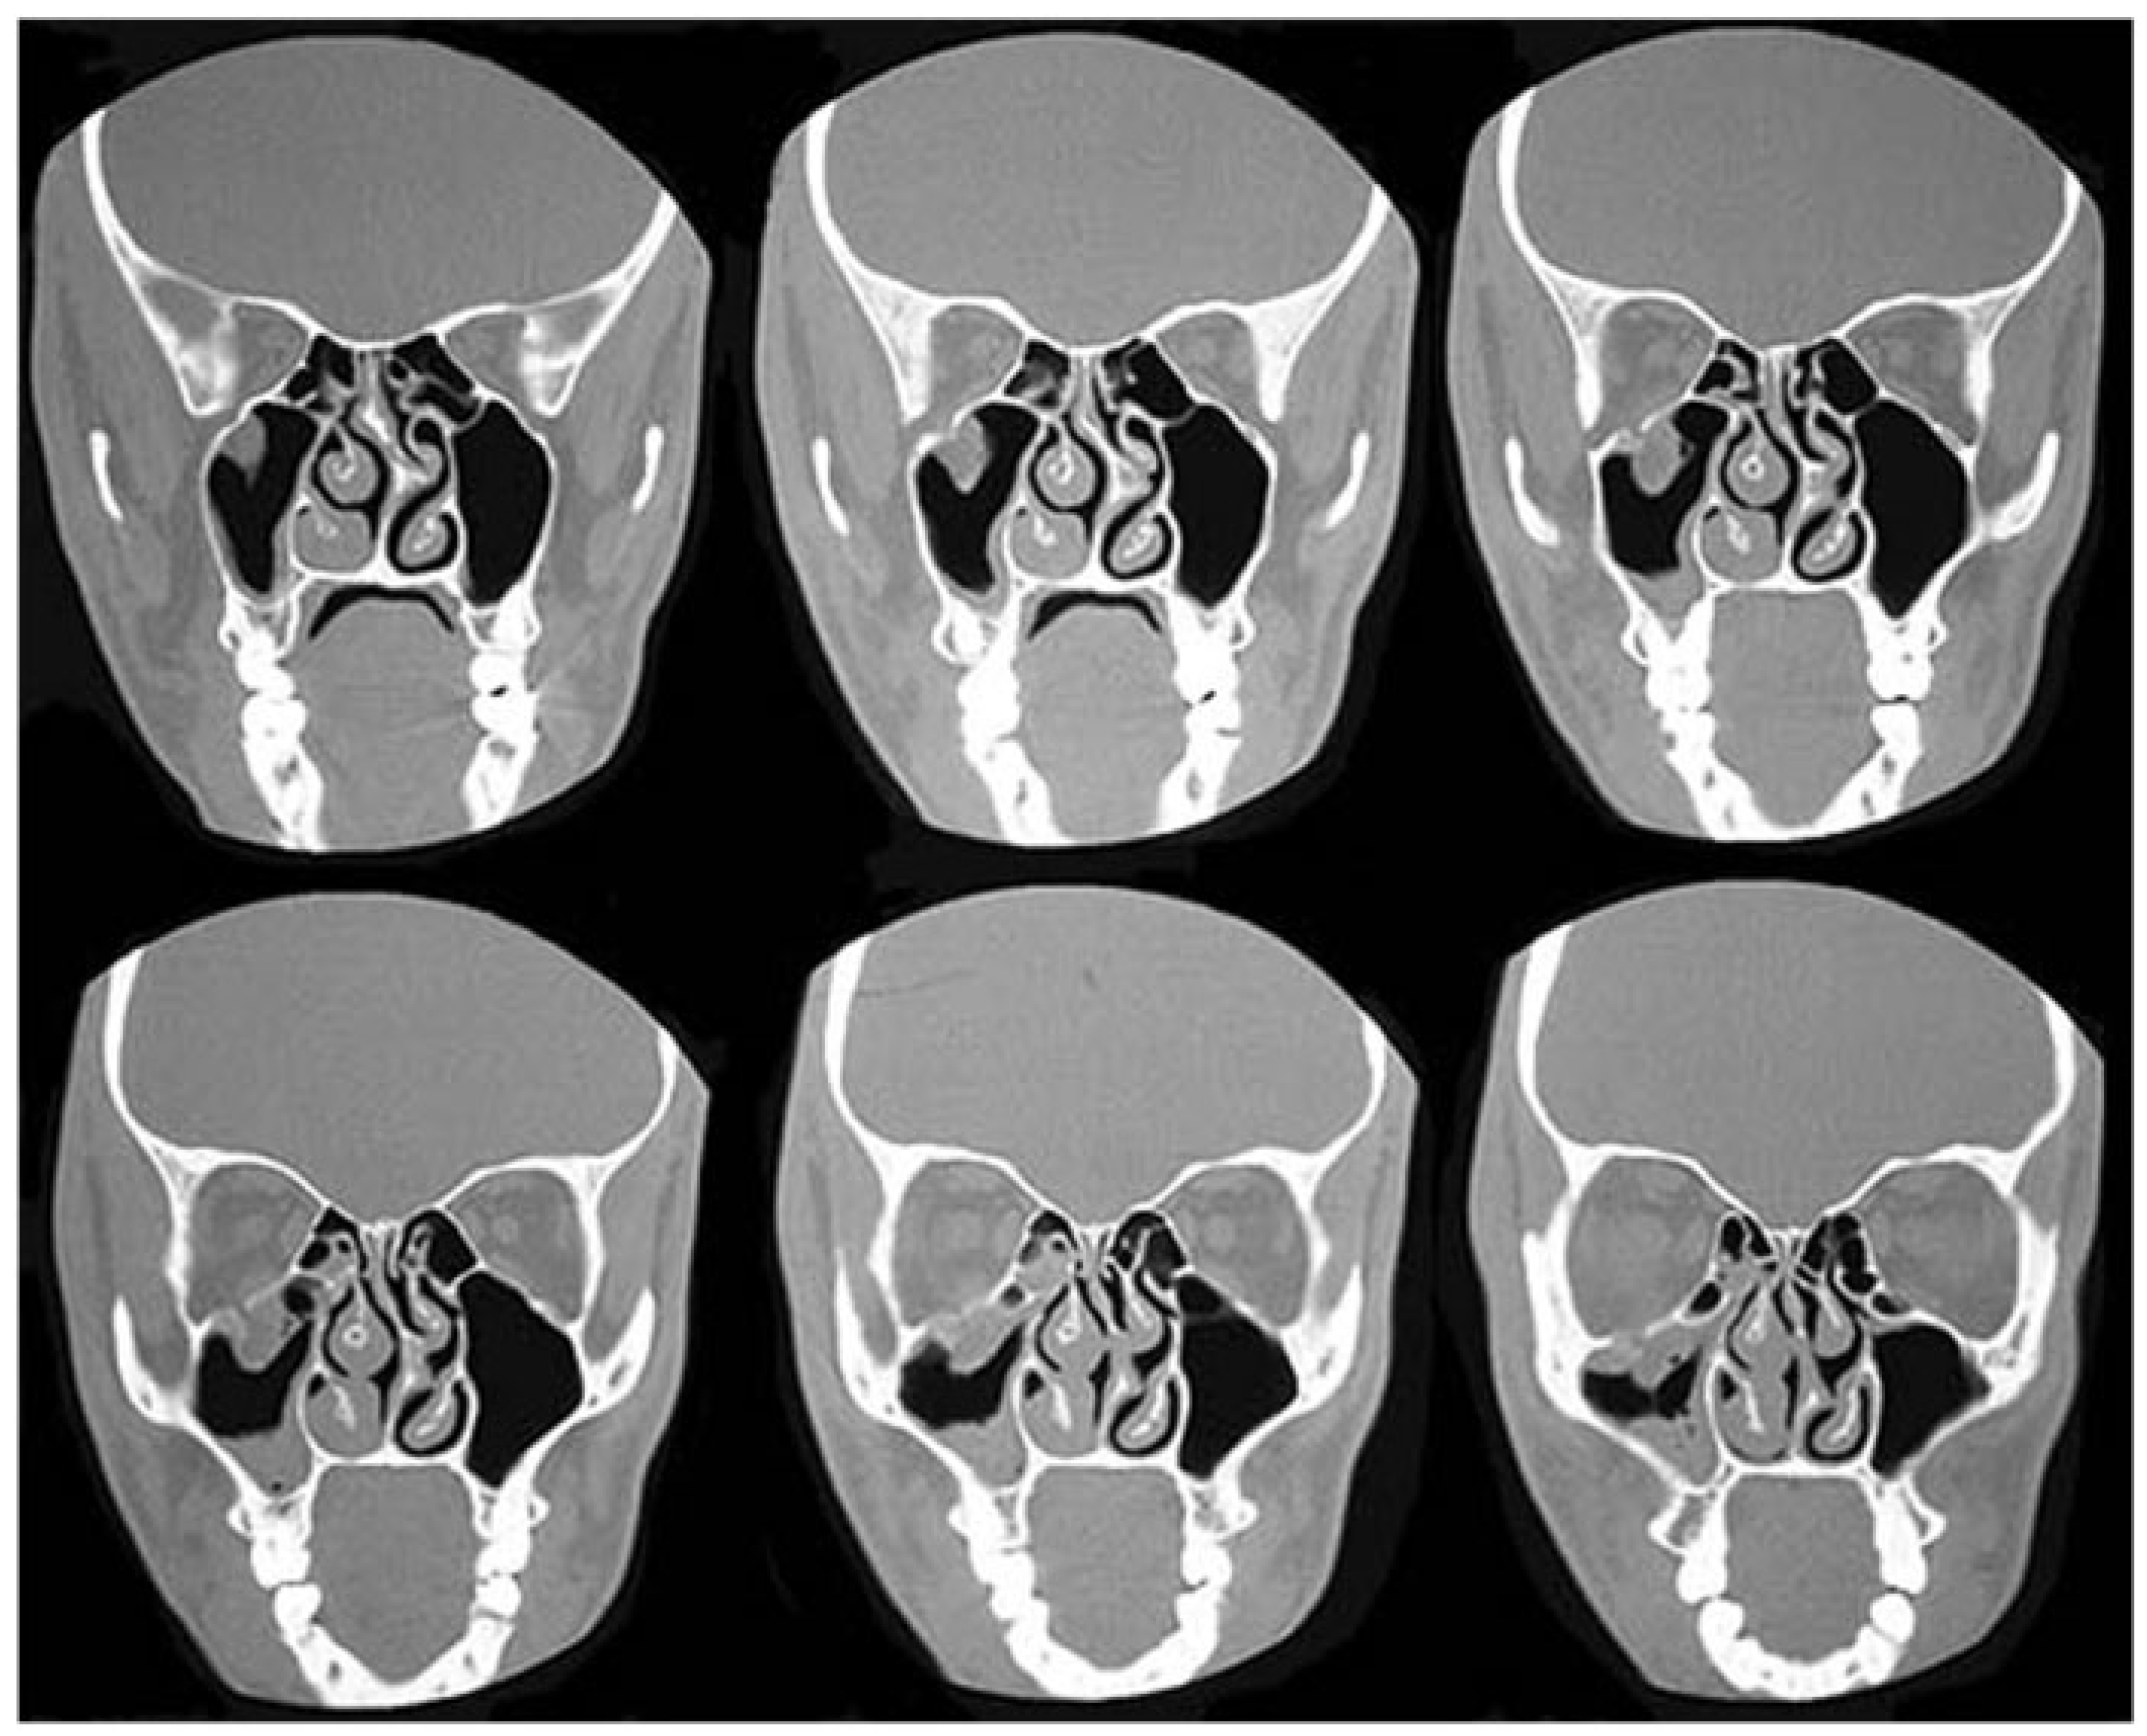

Seven bones make up the orbit: frontal, maxilla, zygoma, ethmoid, lacrimal, greater and lesser wings of the sphenoid, and palatine. The outer rim of the orbit is comprised of the first three robust bony elements, protecting the more delicate internal bones of the orbital cavity. The orbital cavity is itself bound by the orbital roof, lateral and medial walls, and orbital floor. Some of these boundaries display changes in structural integrity—closely related to sinus pneumatization—during different stages of development. On viewing the cross-sectional anatomy of pediatric and adult skulls (Figure 1), the striking bony differences that occur with sinus development become obvious, revealing their relative strengths and weaknesses.

Figure 1. Coronal sections of the pediatric and adult orbit. (A) The thick pediatric orbital floor is contrasted with its diminutive orbital roof. (B) The delicate nature of the adult orbital floor and medial wall is apparent.